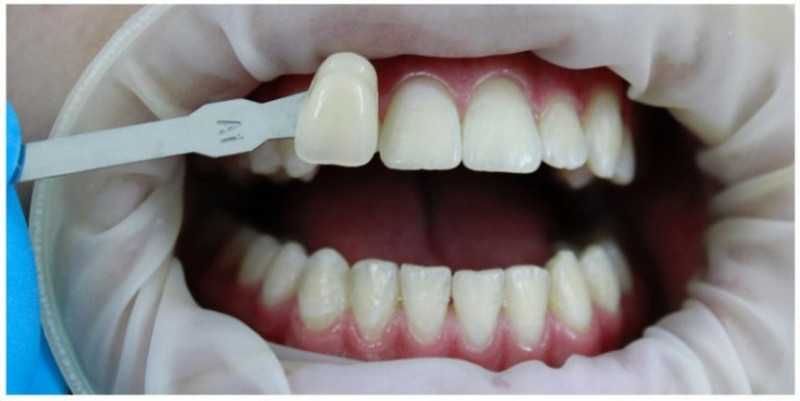

Стоматологическая клиника АЛДЕНТ

Отбеливание зубов

Безопасное световое отбеливание немецкой системой FLASH. Результат после первой процедуры отбеливания

Доктор: Гиниятуллина Алина Ильнуровна